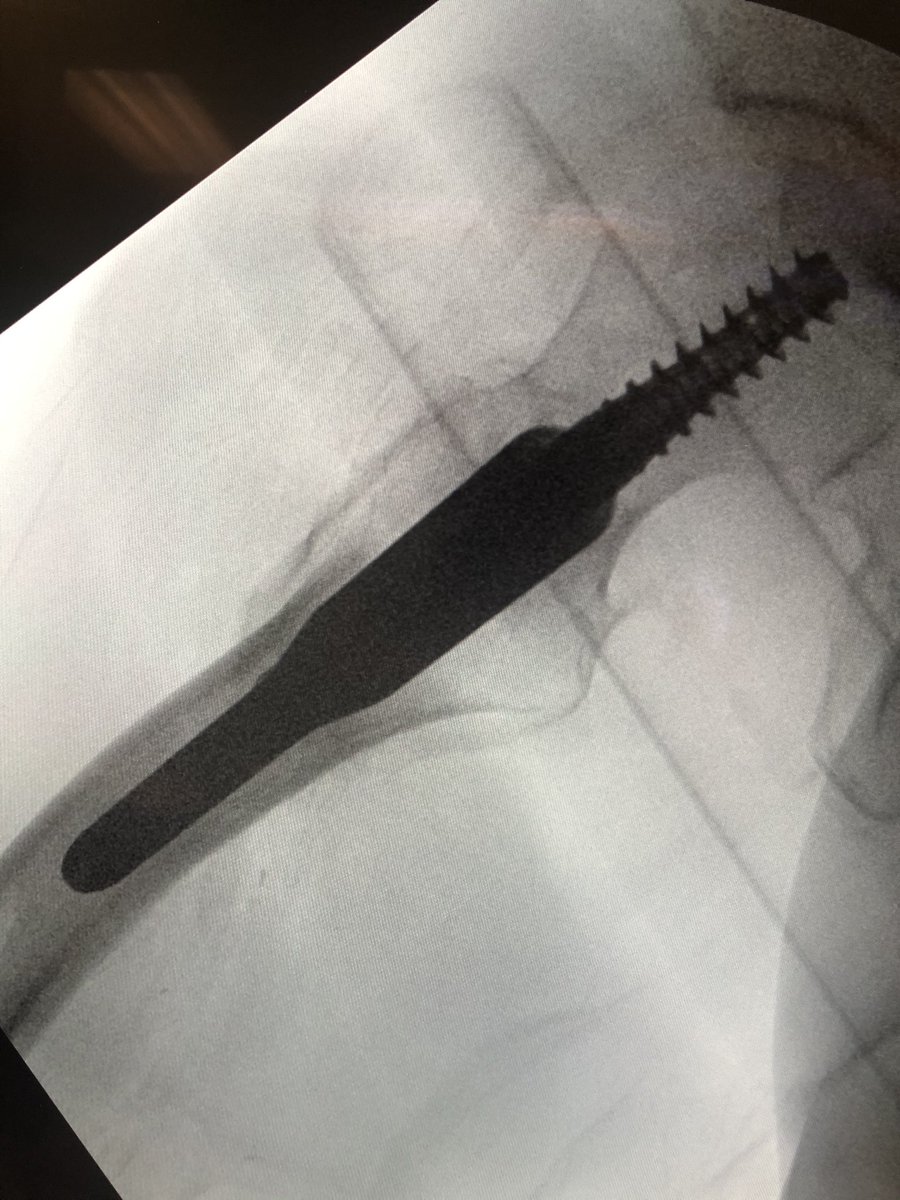

[13/18] When drilling/inserting screw, I usually do it on fluoro, I don’t just rely on the stopping point of sleeves because sometimes you can drive guidewire into pelvis. Also wire can come back out with drill so you need to be ready with obturator or another wire to stop it.

[14/18] If you line up screw handle with the line of the femur (blue) your screw end will be in the right plane. If it’s a left hip (clockwise screwing can flex the proximal fragment) I also build in an extra turn to derotate the proximal fragment if needed.

[15/18] I always try to build in some compression. The place to watch is the inferior medial portion of the fracture (arrow). Don’t overdo it or the nail starts to migrate medially.